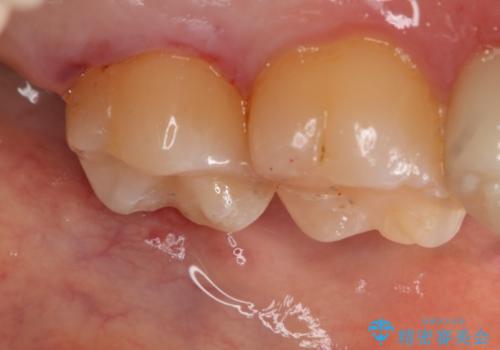

- 左上7番の銀歯のやり変えを希望された患者様です。

セラミックでの治療を希望されたため切削量などを考慮し、セラミックインレーでの治療を計画しました。

銀歯を除去し形態を整えたのち、印象しています。